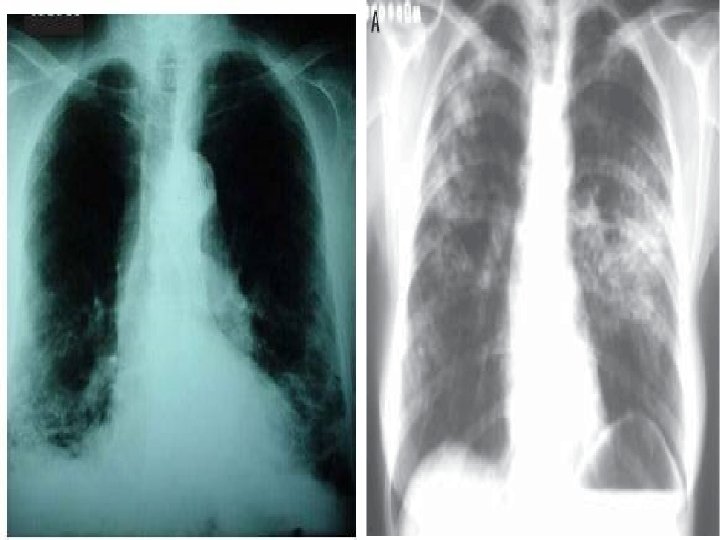

EXAMES LABORATORIAIS (04/10/06): n n n n Uréia: 14 mg% Creatinina: 0, 3 mg% BT: 0, 4 mg% BD: 0, 2 mg% BI: 0, 2 mg% TGO: 42 U/L TGP: 19 U/L Na: 130 m. Eq/L – K: 4, 2 m. Eq/L – Cl: 100 m. Eq/L RX de tórax (05/10/06): Infiltrado em todo o HTD, mais acentuado na base e em LSE e perihilar esquerdo. Seios costofrênicos livres. Coração anatômico. HD: Pneumonia

MANIFESTAÇÕES CLÍNICAS n n Pneumonia por Pneumocystis carinii Aspectos FUNDAMENTAIS: O pico de incidência ocorre entre crianças HIV positivas com menos que 1 ano de vida, principalmente entre os 3 e 6 meses, independente da dosagem de CD 4

MANIFESTAÇÕES CLÍNICAS n n Início Agudo de febre, taquipnéia, dispnéia, hipoxemia progressiva, que pode ocorrer antes dos sintomas. HIPOXEMIA: É comum a ocorrência de hipoxemia sem retenção de CO 2 em pneumonias intersticiais (pneumocistose é a mais provável causa, neste caso).

MANIFESTAÇÕES CLÍNICAS n n Achados da radiografia: infiltrados intersticiais ou doença alveolar difusa que progride rapidamente. Às vezes surgem lesões nodulares, infiltrados raiados ou lobares, derrames pleurais. Diagnóstico: Demonstração do P. carinii por coloração apropriada com prata de lavado broncoalveolar; raramente a biópsia é necessária.